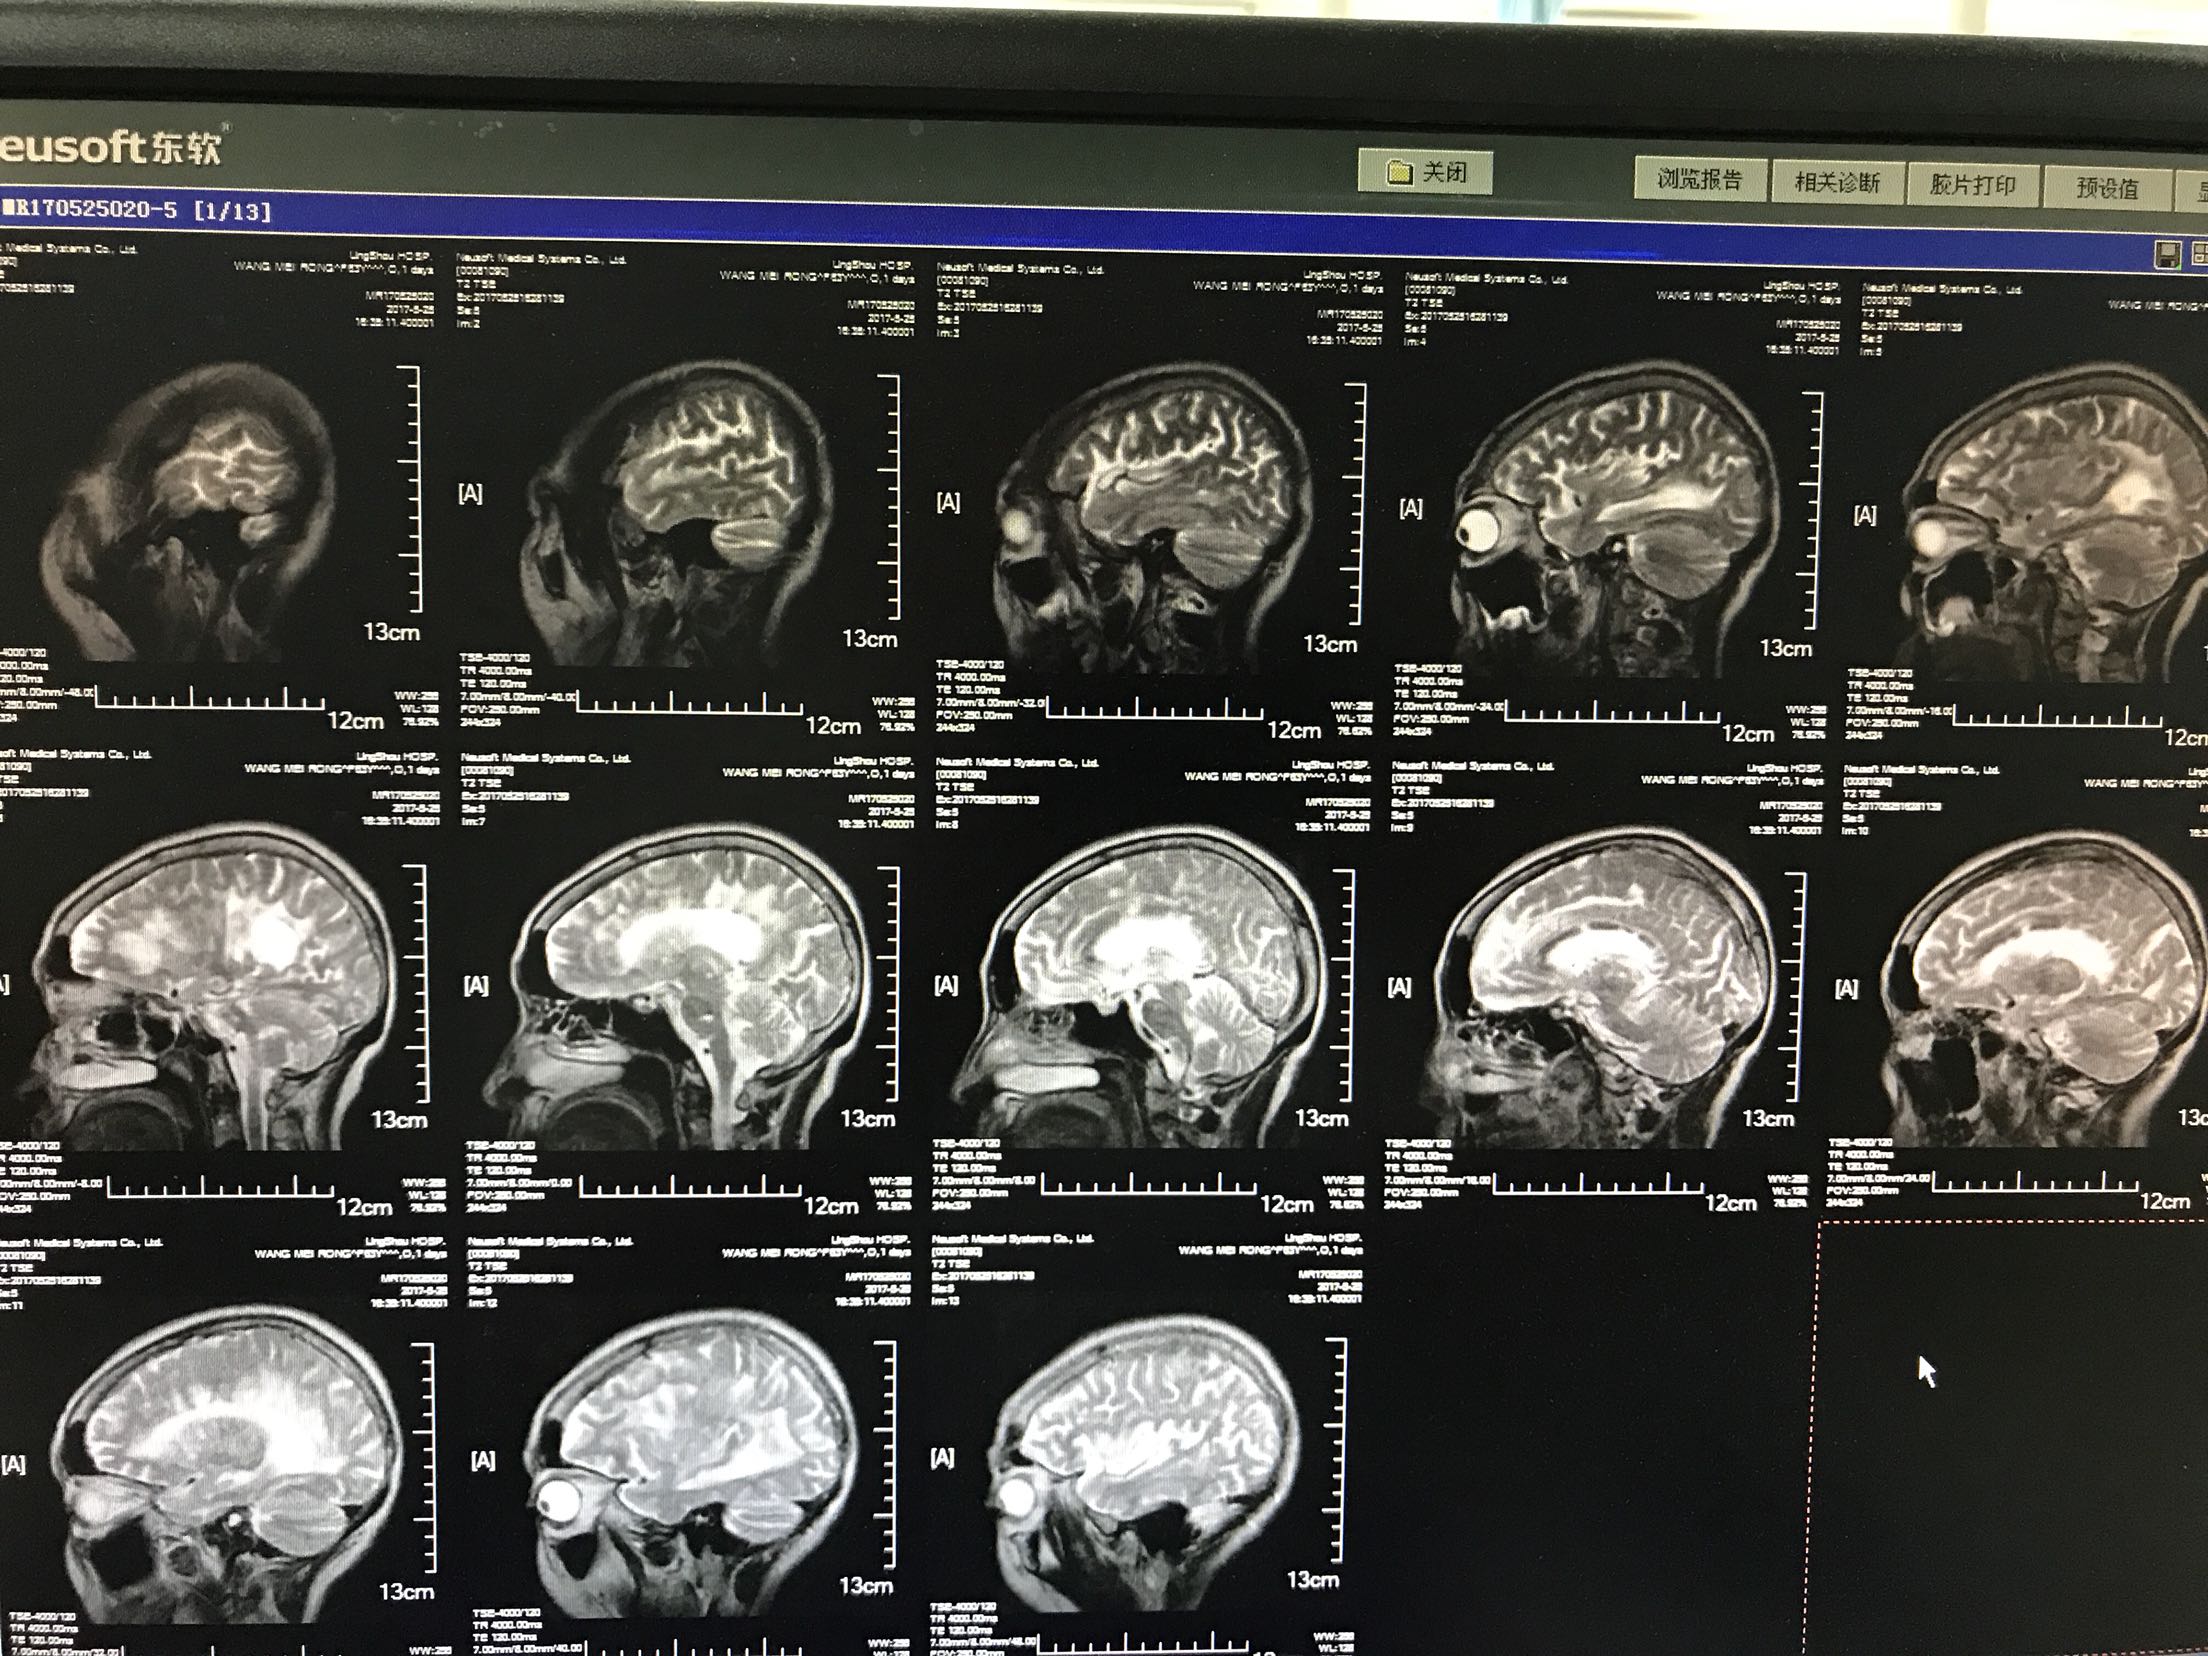

左侧肢体无力加重4小时入院,患者老年女性64岁,既往脑梗死病史10年,长期口服"阿司匹林",曾服用阿托伐他汀,后自行停服!留有左侧肢体无力后遗症,"糖尿病病史"5年,平素不规律服用"二甲双胍缓释片和消渴丸"。自诉血糖控制不佳,有夜间发生低血糖!"高血压"病史5年,长期口服氨氯地平片,具体血压控制不详。患者4小时前无明显诱因出现。左侧肢体无力加重,左上肢可以抬举持物,左下肢尚可负重,能独立行走,急诊查核磁示"脑梗死",收住院

体温37.5℃脉搏95次/分,呼吸22次/分,血压135/87mmhg,神情,言语基本流利,眼动充分,无明显眼震,伸舌居中,颈无抵抗,双肺呼吸音清,未闻及干湿性啰音,心音低钝,心律规整,未闻及杂音,双上肢肌力3级,肌张力增高,左上肢屈曲,双下肢肌力2级肌张力了,左巴氏征阳性,右巴氏征阴性,克氏征阴性,

1.脑梗死2.2型糖尿病3.高血压4.脑梗死后遗症,给于阿司匹林及波立维抑制血小板聚集,短效胰岛素控制血糖,阿乐稳定动脉板块,低分子肝素钙抗凝,降纤酶及脑苷肌肽等静点